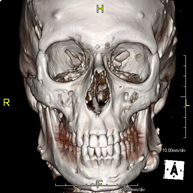

Prova radiològica que consisteix en obtenir imatges del massís facial (cara) d'alta definició anatòmica, mitjançant l'ús d'un equip de TC (Tomografia Computeritzada). Indicacions: tumors, cirurgia plàstica. - TC Oïda

Prova radiològica que consisteix en obtenir imatges dels ossos maxil·lars d'alta definició anatòmica (peces dentals, trajecte del nervi dentari), mitjançant l'ús d'un equip de TC (Tomografia Computeritzada). Indicacions: estudi previ a l'extracció dental, estudi previ als implants, tumors, abscés. - TC Sins paranasals